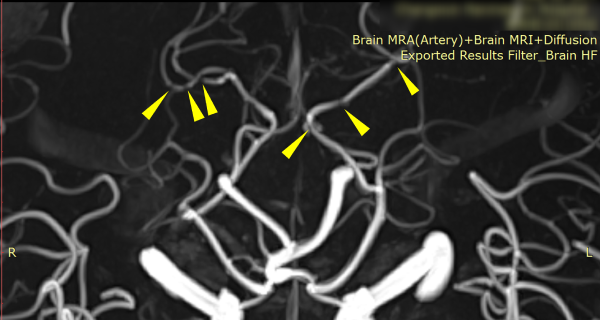

- 3대질환(암,뇌,심장) 진단금 보상전문

- 신경계(뇌출혈,뇌경색) 후유장해 보상전문

- 시리즈4 : MRI 검사 후 반드시 묻게 될 뇌혈관진단금 30가지 질문